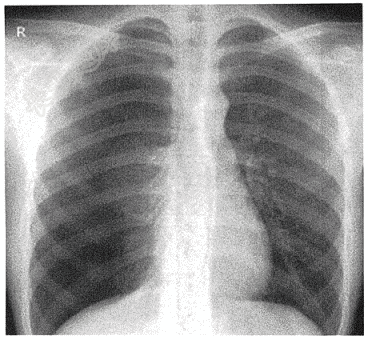

- 单项选择题男性,16岁,胸痛12小时( )

A、右侧气胸

B、右肺炎症

C、右侧液气胸

D、右侧肺炎

E、左侧气胸